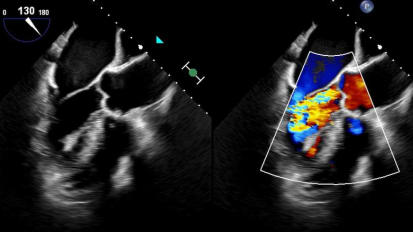

Chapters Transcript Video A Programmatic Approach to Lipid Management in 2023 Dr. Talreja details the epidemiology and pathophysiology of dyslipidemia. I'm honored to be able to talk to you about this topic. A programmatic approach to lipid management in 2023. And I know it's only 2022, but like a good chess match that has a beginning, middle and end game. I've crafted these slides to sort of tell the story of where we are and where we're heading before I do that. I wanna give a quick moment of recognition to the trainees who gave talks at this year's Heart of Innovation program. They were recognized during the program, but our time schedules were a bit messed up. There were a tremendous series of talks from a number of our trainees. They did a fantastic job and I can't wait to see what next year is gonna bring, calling out our 1st, 2nd and tie for third place winners who are getting cash awards. And uh, and the joy of recognition for success, um, kudos to all those and those of you listening as trainees, pay attention to next year's Heart of Innovation Conference. Another chance again, amy will get together with all you guys afterwards with your certificate book and uh, and the award. So part of Innovation again this coming year, I'll launch right into my topic. And I'm gonna tell you, I'm gonna talk really fast. I have a whole lot of slides and I kept trying to condense them and then add more and condense them. This really should be two grand rounds. But since we're ending the year with this one, I only have space for one. These are my disclosures, they're available on the websites as well. So I started with an interest in lipid ology probably a little over a decade ago, one of my partners in cardiovascular associate steve jones lured me into boarding and lipid ology and as I think of the sort of tale of two cities approach to the world. These are the two differences I see in my clinic I get referrals of patients with severe aortic stenosis for trans catheter based aortic valve replacement. Those patients typically have a lot of information at their fingertips and they come in knowing exactly what they want. They've read everything and they know where they want to go. In fact were often the ones sort of slowing them down and saying, well we have to think about surgical options. You may not actually need a valve replacement at this point. So, good job learning. But maybe we're not there yet. The opposite is the lipid clinic where the typical consult is a patient who has read this among many books and is skeptical of what is again, clearly lifesaving technology. That has a tremendous value proposition. And it's a real tragedy because as a result it limits what we achieve in prevention, which really is the key at the end of the day. So today we're gonna talk about some epidemiology and path of physiology of dis lipid e mia. We'll talk about lifestyle options and specifically the tremendous opportunities that exist in our community for really changing the course of a disease trajectory for atherosclerotic cardiovascular disease. We'll talk about pharma co therapy options and I'm gonna blitz through quick look at data and what's available and what's new integrated throughout this and especially at the end will be guidelines. And then we'll talk about the lipid program where it is and where it's going. So atherosclerotic cardiovascular disease in 2020 is estimated to affect 30 million Americans 19 million. So two thirds roughly are on statin therapy for some form of this disease entity. 15 million receiving statin therapy were not at the A. C. C. H. A. Recommended goal of an L. D. L. Less than 70. So shocking in this era that we really have so much. We're not even at the halfway point in terms of achieving what we set out as our goals. Obviously atherosclerotic cardiovascular disease is a heterogeneous group of diseases. Those of us in cardiology so often think of coronary disease dancing ACUTE. M. I. Semis and so forth. But stroke P. I. A. And P. A. D. Including aortic disease are really a part of this uh different spectrum of disease. Over the last three decades we've seen a tremendous improvement in cardiovascular mortality. Unfortunately over the last most recent decade of those 3 to 4 decades we actually seeing now an increase in deaths attributable to cardiovascular disease independent of definition. Some of this is perhaps catch up you know no one's immortal and so as we make people live a decade longer eventually we're going to run the course on that time. But some of this is a more complex disease process and there's a lot of other factors this slide calls out in diabetics in particular. We've made tremendous inroads with new therapies and the last time I gave a grand rounds on this topic, Elias carriage from the VMS endocrinology department joined me and he talked about management of diabetics after I talked about methodology. Um what we see again and again is even with the newest therapies, you know think of S. G. L. T. Two inhibitors GLP one ras and other therapies. We have insulin pumps. A diabetic patient still has a 1.5 fold increase in the risk of cardiovascular death compared to the general population leaving that as a particularly vulnerable population. The reason is, and we know the molecular level of what's going on in quite some detail. Amazingly enough, I will say of all the boards I've taken the lipid boards were the most nitpicky and hardest to understand. And part of it is the path of physiology we're talking about here is so complicated that even when you sit down and try to draw out everything we know there are huge gaps in the mechanisms that work. But what we do know is a probie bearing lipoproteins. Think of LDL and particles like that are really where the action's at in terms of creating inflammation in the vessel starting the process of plaque accumulation and going on to create ultimate calcification. We know a lot about lipid metabolism. The average american consumes 200 to 400 mg of cholesterol a day. The average american produces between 612 100 mg of cholesterol a day. So bad diet plus good genes or good diet plus bad genes leave us with some variability in how patients respond. We know HDL can be beneficial. We know LDL and the particles like it can ultimately lead to plaque accumulation. And ultimately, If you want to think of this in a fairly simplistic fashion, it's LDL level, circulating LDL times the number of years of exposure to it. That equals your total plaque burden and causes atherosclerotic cardiovascular disease. We can't affect time directly, but we can get patients on good therapy and give them a long run on that good therapy to try to prevent accumulation of plaque and that's really the goal of everything we're talking about in the next 40 minutes. So first and foremost, let's talk about lifestyle modification. This is clearly underutilized, although we've made a lot of inroads in this, calling out the 2022 American Heart Association statement on the comprehensive management of cardiovascular risk factors for adults with type two diabetes. We see that lifestyle modifications are the first thing we think about quitting smoking, exercising, eating right, losing weight. Then we think about social determinants of health. We think of cardiovascular imaging, I think in this era we still massively underutilized, fairly inexpensive tests. Think of coronary calcium scores. Think of cT imaging. We have great stress testing and for those patients that needed cardiac catheterization. But compared to a decade ago, there's there's obviously a lot of ways to pick this process up early in the game. And then we have a great number of medications, especially in the general population and in diabetics that can impact this disease process quitting smoking. I'm just gonna show this slide enough said critical, critical um dietary patterns. This is from an A. H a publication plant based diet will call out specifically as what recognizes one of the healthiest diets out there now. Of course no diet is effective if a patient is not going to follow it. So there are other opportunities available for us. And we've done study work on some of these, I will say, unfortunately, the worst diet out there fits with our geographic location. The southern diet is really the one that is known to increase the risk of cardiovascular disease and heart failure. Physical activity. Any level helps increasing mets, especially up to uh the relatively moderate level has a dramatic impact on all cause mortality. And that's why cardiac rehab programs are so useful. It's tough practicing cardiology in your local community for those of us that want to go out and grab some fast food, you have to hide if you're a cardiologist, I don't get there much. But among the billions and billions served. I try to be not in that pool too much and most of our patients need to do the same. So years ago, almost a decade ago we did a study. Many of the folks in this room were part of this are supported one way or another an investigation of four commonly used diet, plant based mediterranean, paleolithic and dash diets. I showed this in a forum here, but it's been about a decade. This is collaboration between our area and the University of Virginia. We offered 100 patients that self selected their their arm. Four commonly recommended diets and what we saw was interesting just quickly calling out everyone lost weight or every group lost weight anywhere from 4 to 5 up to £12 over a period of 60 days. B. M. I improved blood pressure improved pretty remarkably. This is what you would expect from one or two medications. An average blood pressure drops systolic a between 10 and 15 mm of mercury. For patients that complied and calling out some lipid changes. We saw pretty impressive reductions in everything from triglycerides to LDL, including highly specific markers like L. D. L. P. You see in this, the vegan group really had the most remarkable decrease in LDL. P. 100 and 40 point decline. Diet is extremely effective. Now this was a decade ago. What about since then I'm gonna come back to our rehab programs. I've worked with them to get some of the data from our patients locally over the last quarter for those patients who can't get where they need to be or starting too late in the game for diet to be sufficient pharma co therapy becomes important. There are a lot of trials in this spectrum. These are great trials. We participated in a lot of them and we'll talk about some of the key ones as we look at what's going on. So if we think about lipid lowering agents, our mechanistic understanding of what's going on has allowed the development and testing of specific agents and this is from the journal American College of Cardiology. There are five specific mechanisms called out here. Number two is our H M G. Co a reductase inhibitors statins, very effective, very underutilized patients are very well aware of the potential side effect mechanism. And importantly, even with statins which are the 1st, 2nd and 3rd line therapy, a lot of patients we looked at the numbers earlier cannot get to their target therapy, whether it's related to compliance or insufficient potency. One above the status in the same pathway of production of cholesterol within the parasite is a teepee citrate lies we have a blocker for that which works upstream of statins and can be used with them. That's empathetic acid. Number three. The NPC one. L one receptor is where um I've works and we'll look at that Number four is through interactions with the pcs K nine protein. And that's where we have new injectable agents that can act directly on that. And then today we'll talk about one of the newest editions which actually works on blocking the transcription of M. RNA for pcs canine production and we'll call all those out and the mechanisms to come. So first we always have to think first and foremost in pharma co therapy about statins. There is absolutely no uncertainty whatsoever about the effectiveness of statins in reducing cardiovascular disease. This is the largest meta analysis of almost 100,000 patients showing reduction in every important endpoint all cause mortality, coronary mortality, M. I. C. H. D. Death stroke and major vascular events. Of course there are some patients that have difficulty tolerating these agents but there's absolutely no question that the value proposition, generic, inexpensive costs with tremendous benefit is there. And so it's incumbent on us to try multiple statins at the highest doses patients, patients can ultimately tolerate in all patients. And again, if you look at these trajectory curves, you've all seen many times before whether we're talking about the secondary prevention curve on the top which has a steeper benefit curve or the primary prevention group which has a slightly shallower benefit curve. There is zero questions across all populations as we lower LDL with statins and actually many non statin therapies follow the same curve. But in this slide we call out, lower is better with statins and we really have to be aggressive about it enough. Said I know this is obvious everyone knows it but it's important to call out again. Where that leaves us though is if you look at the major trials of status in every single trial concorde only statins lower event rate, but there's a pretty high residual event rate in each of the trials as well. You see statistically significant benefits. But we see a 25 to 40% residual risk for recurrent events across every trial. Every population we've looked at and that's the group. We have to do more for so many years ago we were in the improvement study that tested the addition of a on top of statin. There's a lot of things you can criticize. But ultimately what that trial showed us is effectiveness of um I've it took about seven years for the curves to reach statistical significance. It takes a while. But the group on combined as a team I've and statin does better with the number needed to treat a 50 that's statistically significant. And that's why again, is another generically available agent. There is a clear utility for this and we'll look at where it falls in the guidelines more recently, the introduction of psychedelic acid has given us another mechanism to affect lipid production within the liver. Some potential benefits of this are it works in a different area than H. M G co a reductase inhibitors, although it's in the same basic pathway, it is a pro drug that has to be converted to its active element. And interestingly in skeletal muscle there's no conversion enzyme. So in theory potentially less skeletal muscle concern with the OIC acid than we see with statins. So gives us one other option and studies have shown us. While outcome studies are still pending, we have clear data that shows about 15-20% reduction in the largest trials trials compared to placebo for the addition of the OIC acid to a satin. And when we look at the combination of a demise and um and and and talk acid together which is one combination pill, we can get up to a 40% additional reduction. So another therapy, again, no hard points yet, those trials are ongoing but this can be effective in patients either statin intolerant or can't get to their max benefit. Everyone here knows about PCSK nine inhibitors. Again, really, a remarkable example of the benefits of understanding molecular level pathways from initial identification of the relevant genetics and populations out there to FDA approval and outcome studies, we're looking at a period of under 15 years to get this therapy available to us. The idea is P C S K nine is an enzyme our body produces on the left. It's the things that looks like cheetos and orange color and what they do is when they couple together with an LDL particle and an LDL receptor, the PCSK nine results in degradation of that LDL receptor, you destroy your own LDL receptors. They finessed over time. Each LDL receptor recycles about 100 and 50 to 200 times. And this is the natural sin essence mechanism. There are people who genetically don't make pcs K nine and they have a lot of extra LDL receptors because they stay in circulation and they work longer. They tend to have low LDL. And so we've replicated this with available mechanisms based on current molecular biology. Um this is lucca mob one of the available ones monthly or every two week injectable agents available multiple trials in the Oslo program that show us very effective reduction in LDL cholesterol. The LDL has dropped by about 50 to 60% across studies and it's a durable effect with potentially a monthly injection for this. Initial costs were high. Those costs have come down as coverage has improved. And now, in addition to proving that we can get a much larger number of patients to their LDL goals, we see outcomes. This is the LDL cholesterol goals. If you look at the LDL goal on the left of an LDL less than 100 we see that in the standard care therapy which includes statins, diet nutrition and the Hamid, about a quarter of patients are getting to that LDL target of less than 100. If you're looking for the LDL target of less than 70 it's under 5% of patients with traditional therapy in that high risk group that get there when you add PCS canine inhibition onto that, it's not 100% but we're getting 90% now to the target of less than 100 and three quarters of patients to that target of less than 70. So tremendous impact on LDL cholesterol and LDL concentration. For a long time. I think many providers wanted to see the outcomes data. We do have multiple trials showing us that correlates with what we would expect an improvement in cardiovascular outcomes. Hard outcomes including death, M. I. And unstable angina and outcomes including coronary vascular ization, stroke tia and even heart failure. You see standard of care alone is effective compared to the general population, but when you add in the PCSK nine inhibitor on top of that, you have a very significant improvement in overall outcomes. I have talked fast. I've gone through a lot of the things that I think have been with us through the last iteration of the guidelines. The 2018 american Heart Association and american College of Cardiology guidelines. So I'm gonna slow down a tiny bit as I go into newer therapies because I think this is the area where folks are a little bit less familiar, just recapping, we've talked about the disease process the burden of disease and deficits in our treatment strategies. We've talked about why lifestyle modification is critically important as the first step and we have to keep coming back to it. It's a battle that's never won. It's like keeping my house clean just after I get it all clean, it seems like it's starting to get dirty again and I got to start from scratch. And then we've talked about a lot of the the conventional therapies we've had available from statins to and there's older ones that are available to the data points are a little weaker for some of those but they are in the guidelines in the interest of time. I've left them aside and then we've culminated with the PCSK nine inhibitors. So now where science has taken us next is the RNA based therapies and I'll give a light dusting of the surface of this topic. There's a lot more to come. And the world of lipid ology is where there's a huge amount coming in this arena as we think on the far right of the slide about M. RNA back to our our days of uh of biology and biochemistry. So M. R. N. A. Is what's transcribed or transcribed from D. N. A. And translated into protein. M. R. N. A. Is sort of the working blueprints that allow our bodies to produce the proteins that actually cause things to happen. And so when that M RNA is translated, we make things like for example PCS canine. We talked about where PCS canine sort of works against us by degrading our own LDL receptors. There are two types now of commonly used RNA therapy. Moving to the left side of the slide here. Anti sense RNA are double are single stranded RNA that are a complement to the other side, making a double stranded um um molecule. So remember DNA double stranded, we transcribed one of the strands and make a single stranded messenger RNA. Back thinking back to A T. G. C. And all those things. If we make a compliment to that we'll now use that complement in circulation if you can get it into the cytoplasm to bind with the matching M. R. N. A. So you can target a specific blueprint specific M. R. N. A. And gum up the works so that you're not going to produce that protein. So you can imagine how that can be used to stop the body from making something like C. C. S. K. Nine. There are also small interfering RNA. These are actually double stranded RNA. Again you have to get them to where they have to go but they're going to ultimately gum up that process of translating the M. RNA into the protein. And so these are techniques we're gonna see more and more, the durability is longer than with the traditional oral agent but these agents can be consumed orally currently although there's interesting work going on in that realm. So now we're gonna talk about in clustering and so PCSK nine inhibitors let's focus on the left side of the slide in a traditional human body. What's happening is our body is translating messenger RNA A making the enzyme PCS canine, releasing it to the cell surface. The pCS canine is coupling with an LDL particle and with an LDL receptor as that endorse it, toast the LDL receptor is destroyed and we lose a valuable tool for getting rid of cholesterol in our circulation. So PCSK nine inhibitors, the traditional ones we've thought about our monoclonal antibodies that once that PCS canine enzyme is released into circulation, destroy it, they bind to it and use our immune system to clear it. We're kind of getting to it after it's gone out into circulation. And obviously uh if you think about it we're never gonna catch 100% of them. So another effective technique which is where in clustering works is to use this M RNA technology to stop the synthesis of PCS K nine in the first place. Now again you're not going to stop 100% of it but you're gonna have less circulating PCSK A nine and as a result you're going to have more circulating LDL receptors. So the mechanism is very similar to what we're already familiar with with monoclonal antibodies to attack this. Some interesting differences are that this therapy is given typically after its initial loading as accused six month therapy which which opens up the opportunity especially in patients that are potentially less compliant to have every six month therapy that could be given potentially in the office on top of that it can be used in addition to the other therapies, including monoclonal antibodies to PCS canine we talked about in the Orion series of trials. This is one of the trials we see again a sustained and highly potent reduction in LDL cholesterol of about 50 to 60% once again. So yet another tool in our armamentarium here accused six monthly injections trying to keep an eye on my time as I go to. Alright, I'm making a good pace. I know I'm going fast. Um It is interesting as we think about this technology. There are a number of RNA based drugs in development in testing and we've already seen the first ones come available to us more coming. We've seen the effect on the far left for PCS canine antagonism and now we're looking at trials coming out which will be my next grand rounds in a year on a pOSI three on a po A And also on and P. T. L. three. We'll talk a little about that in the in the time to come so we can impact multiple different lipoproteins and hopefully further affect this disease process where we still have residual risk left behind. It is interesting one question that often comes up is so what about triglycerides? What about HDL HDL therapies to date besides exercise, low doses of alcohol and uh cessation of tobacco use have been largely ineffective in improving mortality outcomes. So HDL is very difficult to figure out right now. Triglycerides. We know that if you look at epidemiologic data, high triglycerides correlate to increased disease risk. It's unclear whether that's causal or whether it's related to an other underlying disease process. But we'll come back to triglycerides. I could give a whole other grand rounds on that. I've included just a little bit because again looking at trials, there is some benefit there I mentioned briefly and PTL three. I also want to talk about um this uh this group of patients with homocide. FH those patients are rarer so if you think about it we have patients with familial hypercholesterolemia. That's a disease where the genes for the LDL receptor don't work well. Um Homocide FH is when a patient has two broken genes um There are five patients I follow in the lipid clinic in this region with homos. I guess FH it's rare. Heterocyclic FH is much more common. This disease process results in early mortality, catastrophic levels of disease. And there are many different criteria. We can do genetic testing for it. And what's complicated is there are a lot of genes involved. Some of them are the LDL receptors. Some of them are other things like a po B. And P. C. S. K. Nine. We can't identify them. All genetic testing is useful but can be expensive. There's a lot of stuff we have to test and the genetics are pretty interesting because you can have um double heterocyclic compounds. Heterocyclic or identical um home they can have two of the same broken gene or two different types of genes. Um Family members have to be screened. There has to be some form of genetic counseling and typically they have very high LDL. I'm not talking about their total cholesterol. Their LDL can be 400 to 600. And frankly any time you see someone on therapy who has an LDL greater than 300 you should think of this disease condition. These patients need the kitchen sink thrown at them. They need aggressive diet change. They typically need to be on 34 or five therapies. We often did L. D. L. A. For reasons for these patients which is inconvenient and difficult to arrange and not widely available. But recently a different mechanistic pathway. Different mechanistic pathway has been employed to treat these patients. And if we look at another injectable therapy avenue ca mob. This is a therapy that utilizes a different pathway. Now this is an oversimplified pathway. But let me explain what's happening on the far left. You see the liver is producing V. L. D. L. The LDL particles. Very low density lipoproteins are metabolized through like phases the lipoprotein lips. The red LPL and cecilia like paces the red E. L. Into the LDL remnants, intermediate density lipoproteins and then ultimately go on to form LDL. Which is what we typically think of in some genetic disorders, patients can have excessive levels of just the LDL itself. But typically if you think of the average patient in this pathway, it's the lie paises that push the particles along and there's this enzyme and PTL three and important like protein three that inhibits the life. Now if you now follow the circuit around so you go down to the bottom through the LDL LDL particles and you see those are taken up in the liver by the LDL receptors which are those spaceship shaped purple things on the bottom of the liver. So in a typical patient we secrete the LDL metabolize it, take the LDL back up into the liver and get rid of it. And that's where for example are PCSK nine inhibitors are so useful. Uh Right because they increase the number of LDL receptors. But now you imagine the poor patient who has nonfunctional LDL receptors, we can give them more of those receptors but they're not working in the first place. And so we're gonna have limited efficacy to just ramping up LDL receptors which is ultimately what statins zita, my psychedelic acid and all our forms of PCSK nine inhibition do. It turns out there's another way to get cholesterol out of circulation. We have V. L. D. L. Remnant receptors which are the green space ships on the side of the liver there and so there's a secondary mechanism completely independent of LDL receptors to get rid of these particles. And that's what does is it up regulates that the LDL receptor receptor receptor remnant uptake. What it does is it blocks the ndp TL three and through a complicated mechanism that's not entirely uh you know clearly laid out in this slide because it's super complicated. What happens is you get more V. LDL remnants taken up by those remnant receptors which are largely functional in these patients who have non functional LDL receptors. And what happens when you give patients this therapy This therapy is a once monthly therapy now it's not a sub Q injection, it's an infusion that's given. But what it does is it reduces LDL in these homocide FH patients another again around 50%. It seems like every time I show you a therapy I say it reduces LDL by 50%. That is kind of what the data shows. So with these newer generation of therapies this is approved for Homo ZegaS F. H. This is not for your hetero zygotes or other patients. Yet interesting trials will be ongoing but for that group of patients the unique mechanism makes absolute sense. And this can be again a really impressive add on therapy we still like to use the other therapies and those patients. And in fact this 50% reduction is on top of in the trials, I don't have enough time to go into all the data. But those patients who are largely on three or more therapies, including Pcs canine therapies um on a crisis on limited pied, which is an older therapy really isolated for those patients. And so now we've looked at a bunch of different, newer injectable therapies from PCS canine therapies to imply sarin now to even upthe map. And so the world moved ever forward with this. As with so many things, I think many times it's overwhelming to the average clinician out there who has, you know, 15 or 20 minutes to see a patient. Our staff does tremendous work to help us get preauthorizations and so forth. This is why in the slides to show you, I'll go over, we have the lipid clinic available for those patients who identify that needs some of these more aggressive therapies. Please do not hesitate to reach out to me or anyone on our team that can help and try to make this happen for patients. Last thing in terms of pharma co therapies I think has to be called out because it's been an area of controversy over the last decade is E. P. A. And D. H. A. Therapy. So we're talking about omega three fatty acids. We're talking about fish oil here. There are some plant based versions recent trials have made us suspect that there really is a difference between E. P A. And D. H. A. Both of which are the traditional omega three fatty acids, E. P. A. And D. H. A. Combined trials generally haven't shown a hard endpoint benefits. But to really important trials, the jealous trial and we'll look at reduce it shows specific reductions in cardiovascular endpoints on E. P. A specific formulations and there's some mechanistic reasons why that might work. But reduce it. Just to call out this trial looked at 8000 patients with pretty well controlled LDL and triglycerides of 1 35 to basically 500 with risk factors like diabetes for cardiovascular disease And what they showed that was impressive and consistent with the previous jealous trial is reduction in both the softer primary endpoints of CV death. My stroke and also unstable engine and revascularization. Those latter two make it softer but also of the harder cd det M. I. And stroke. You see statistically significant reductions. You see the p values are much much less than 0.5 and you see numbers needed to treat of 20 to 30 in this situation. So kind of a breath of life back into thinking really about the appropriate patient with that moderate elevation of triglycerides for using E. P. A specific formulation. So the guidelines, there's a lot of them. The last time I gave this talk in full version and we looked at guidelines was when the 2018 A. C. C. H. A guidelines came out. I didn't love those guidelines because I thought they left more to clinician judgment than they specified. But first let me take a second and pause and talk about this because at the end of me showing you a bunch of guidelines really quickly. This is where we're headed 2018 H. A. C c 2019 european Society of Cardiology. To the right of it. To the right of that is the 201988 guidelines. And to the right of that is the 2017 American Association of Clinical Endocrinology Guidelines. You see what's changed from the old days when many of us trained is there's been the addition on top of low medium and high risk of very high risk and even extreme risk patients. What gets you into. I know I'm not sure how to get that. Even super fantabulous risk will be like the next one I think after that. But but these patients are out there and the idea is we really have to be aggressive with these patients it's not enough to quit and say yeah they're kind of high risk. Those patients that continue to have events continue to smoke, have diabetes and even a lot of simpler stuff. I'll be honest with you in the average clinic one of us sees a cardiologist sees there's no one left that's not in that very high or extreme risk group because now that includes anyone with an event within the last year or multiple events who has hypertension or diabetes or is a smoker or chronic kidney disease with an E. G. F. R. Of nothing up to 59. I don't think there's anyone I'm seeing that doesn't fit one of those categories quite honestly anymore. So pretty much everyone now is very high risk of extremists in our clinics. And you see the numbers we're looking for SDL less than 70. Less than 55 based on really excellent data sets that show hard endpoint benefits. I'll go into where these guidelines come from in a really brief sort of pass through the guidelines over the last for the last five years worth of guidelines. But this is where we're headed. LDL is less than 70 and even less than 55 I think it's really easy to pat ourselves on the back to in our guideline order sets, there's hard stopped items for starting patients on statins. You can get out, you can say they're intolerant but often we don't get them onto max tolerated doses. We have a really hard time in this era where clinicians are unavailable. Many of us are booked out for months if not close to a year, titrate has become really difficult and we're gonna we have some solutions for this. I'm just pointing out the problem first. So the 2018 H. A guidelines, these are now out of date and yet still we're not even at this level yet, these guidelines say that for secondary prevention you've got to get the LDL hopefully below 70. And if they started out with an LDL of 71 it's not enough to get them down by one point and claim victory. You need a 50% reduction from where they were when they started. So that patient that comes in with an acute M. I. And has an L. D. L. 71. If you read the guidelines really, what they're saying is you got to get them down further. So we got to set the target lower and lower. Um aggressive risk scoring is important. And I called out earlier that really I think the future of this field is aggressive imaging early on in these patients, calcium scoring has become very affordable and with the with the current generation of CT scans of chemo in the audience. You know the quality of reads we have locally that there's a lot of room for the diagnosis. Well in advance of that acute stem E actually got a page as I was driving in that there's a stem e headed from Sam see the beach and I wish I could be there doing it right now. But I said I'm on the way to Norfolk already and it's always a tragedy when someone comes in with that notice that back in 2018 the A. C. C. H. A. Kinda really took a very heavily evidence based, they wanted multiple trials with endpoints. They called out Staten Staten Staten Staten Staten and if you couldn't tolerate it then Zetia and a week call out to PCSK nine inhibitors. But they didn't really give us a lot of guidance on newer therapies that fortunately has changed the 2019 guidelines from the european society of Cardiology which tends to run a little bit ahead of us called out that LDL reduction to a goal of less than 55 which now has been called out by a number of other societies. A really thorough and great set of guidelines is the A. C. E. American Association of Clinical Endocrinology guidelines from 2020. The reason I love these guidelines is they are robust. They call out every detail, they talk about all the risk categories. They talk about all the particles. I'm not gonna read through all this, I'm calling it out. So those of you who want to look at a really well written set of guidelines can look at this set. They really call out lifestyle recommendations that we've talked about a little bit. They talk about the targets where you need to get patients what therapies they use. They use both older and newer therapies and they readily call out for instance look at the far left for extreme risk, it's high intensity statin. If they don't get to an L. D. L. Of less than 55 at either Pcs canine Hmeid cole Sullivan epidemic acid. Now remember this is 2020 so we didn't have some of the therapies we talked about today and then they talk about really pushing LDL down, we'll update these in a second. In fact right now, this is the newest set of guidelines. Just fresh hot off the press from the american College of Cardiology and the american heart association. These are expert consensus decision pathway guidelines on newer therapies available. I've cut it short so I can uh just show you basically all the high risk groups. If you can't get the LDL down by 50% or more and get the LDL to less than 70 on max intent intensity statin they specifically call out addition of and again this doesn't have to be sequential but um I'd consider attacking Pcs canine directly. First step is probably your your monoclonal antibodies. Next step is epidemic acid glycerin. And again, we're waiting on hard endpoint trials from those latter two but clearly very effective agents in in our therapeutic armamentarium. And notice how the curve keep cycling cycling you back up. If you don't get the LDL, less than 70 and down by at least 50% then add more, add more, add more. And I think at any point you can either go back and add another agent, there's a clear titrate, an algorithm that exists in this pathway or refer onto lipid specialists. Either one, whatever is gonna get the patient there. And so that leads me to the last topic which is our Sentara cardiology lipid program. So if I look at what's going on, what needs to happen at a health care systems level, There's clearly an urgent need to bridge implementation gaps in health care systems to improve population outcomes. We need to better assess the most important modifiable barriers, whether it's tobacco use, whether it's diet and nutrition, whether it's access to pharmacologic therapy, we need to apply what we've learned from trials and really do what our guidelines are telling us to do and we need to keep on these until we successfully implement these interventions. If the obstacles getting the patient on diet, we have tremendous rehab programs. I'm gonna discuss in a minute if it's for example, getting a patient on therapy either it's their noncompliance, we have to hammer them with that. If it's access to therapies, there's a great partnerships we have with industry to help get patients on therapy when they can and sometimes you tried everything you can. You can't get them on therapy this year. Don't give up try again next six months or a year later. And then we have to get the sustained improvement and focus our patients attention on this. How many times have you seen someone that's had an M. I they're terrified. They're willing to do everything right. And one or two years later they're right back to where they started. We have to keep on these patients. So I mentioned 2023, this is now the end game. This is where we're gonna talk about what we're trying to do in 2023. This is a slide from the central cardiology. 2023 co management metrics on care delivery metric one is ambulatory access. We're trying to get providers available for patients more every system and every subspecialty in the country right now is facing significant shortages in providers and nursing staff and technicians and office front desk staff and everything that makes it possible for our patients to see us and get the care they need. There's tremendous needs right now we have to leverage what staff we have and we have to figure out more effective ways to deliver care. And part of that is getting every provider to work at their highest level of certification. We have tremendous nurses and one of our metrics is develop and implement our end protocols for Hyperloop anemia RN visits beginning by third quarter. We're already doing some of this work and the idea is tight rations instead of getting back into dr McKechnie scheduled to increase the Crestor from 10 to 20 or potentially to add the next drug or the next drug or the next drug on R. R. S. Can help us with that. And so we're gonna start this program and be tracking it and that's one of our key co management metrics Rehab programs. We have a lot of fantastic rehab programs here. They're all tremendous many of you like me here are patient experiences and one of the fun things I think I get to do with post my patients nowadays is every single time my experiences when I talk to a patient about rehab, pretty much 90% of patients. You can see their lack of enthusiasm when I describe the idea that we're gonna put them in cardiac rehab and it's so much fun to see them come back the vast majority after they've done whichever program they chose throughout our community say that's fantastic. Many say I'd like to stick with this forever. And with maintenance programs they often can, although remember we have a shortfall in staff Sharon, Henry and uh and and Dr Penny have done a tremendous job developing the Ornish program at Princess Anne. And there are two main things I want to share, sharing was kind enough to um share with me slides. This is from Q two of 2022. Looking at baseline and nine week measures of dietary fat dietary cholesterol and exercise. And you see changes of 50 to 1000% in stress management techniques and exercise in improvement and diet. A very intensive rehab program. We have a series of standard cardiac rehab programs and then I'm showing you now some of the results from the intensive rehab programs because they're tracked If you look at the princess and specific results, weight loss of 5%, which again fits with the data. I showed you from our independent small little trial earlier cholesterol reductions independent of pharmacologic therapy of almost 20%. LDL went down 25% in these patients, triglycerides down a little over 10% and improvements in blood pressure of 5 to 6% both diastolic and systolic with improvements in depression 10% drop in a one C and up to a 50% improvement in exercise capacity with almost a 50% reduction in reported angina. Many patients get off medications. Um I think it's a tremendous program for those patients that are interested. I think too often we take as an out that this patient probably wouldn't be interested in a vegetarian diet and in fairness many aren't. But one thing I've become increasingly aware of is we should at least give them the choice. We should mention it. We should put the opportunity in front of them and let them think about what they want to that end. Many of us don't have a lot of familiarity with the Ornish program and with what's really involved, Santora's run three separate conferences talking about this program in specific and they've been widely attended in the community. Last time we had to cap it at 1000 people and offer virtual options because there's so much of the community that actually is interested in this. Um What we're working on right now is generating probably in february, what will be a four day program for cardiology providers to participate in the goal is not just to do those four days. We're going to spread it out over a couple of weeks and we're targeting february 2023. We're looking at doing it monday and Wednesday from 4 to 9 p.m. This will be open to the initial program, will be 10 providers will pay out of pocket those of us who want to do it. I'm actually excited to do it and I'm saving a spot for me. And uh, so if any of you want to come join, please email me. There'll be more detail coming. I think if we need to try it for a little bit and see and really commit to a couple of weeks and see what it's all about. Maybe maybe sounds sick with it. Maybe some won't. But I think we all owe it to ourselves to at least think about this option for our patients on top of Ornish. We actually started something new this year. So center is a large system. We have hospitals up and down the state of Virginia and north Carolina. A second intensive cardiac rehab program has just opened that the critic in program critic in is very much like Ornish a little bit less heavy in the meditation side. And this program again is versus traditional cardiac rehab, which is 36 sessions. Mostly exercise with some dietary counseling. This is 72 sessions with exercise and education. It has the potential to offer a different option potentially less expensive because there's a little bit more video work shopping. Again, some of the benefits of an orange type program but maybe uh with a little bit less of the cost, a little bit less and less of the focus. So Ornish is probably still the, you know, the most intense version of this. Uh Sentara Martha jefferson hospital went live with this november 28th and it'll be extremely exciting to see the results and Sentara care plex will go live and anticipated in january of 2023. So what I love about our rehab programs in this area are we're offering the latest, the greatest the cutting edge and multiple options for patients. Why do we need to do all the stuff we talked about it today. This is from the asteroid trial. This is old data. This is 2006. This is when I had all all dark hair and no gray and many of you in the audience that I know and love were in the same category for those of us who start at the same time. Right. This is an actual intra cardiac intravascular ultrasound from a patient enrolled in asteroid. After six months of therapy at baseline. The lumen area of this led was 7.7 millimeter squared and the aroma was almost twice that 13 millimeters squared with aggressive diet, lifestyle exercise and Crestor 40 mg. Six months later, the patient's luminaria had increased from basically seven to basically 10 millimeters squared. And the as Roma was cut basically in half from 13 millimeters squared to seven millimeters squared. And that doesn't even call out the plaque stabilization. We believe that occurs and the reduction in hard endpoints. Am I death and stroke? So summarizing a lot at once and then I'll open up the floor for any comments or thoughts or questions. What we talked about today is we talked about the extreme disease burden that exists, which is tragic in a first world nation where we have great therapies and yet we see an increasing incidence in cardiovascular deaths in the last decade. We talked about a lot of guideline sets and saw how they're very largely concordant. 50% reduction in LDL and LDL targets in the highest risk patients now of less than 55. We talked about conventional therapies. We talk about statins And statins and statins and then we talk about all the newer therapies. What's available, what's approved? What's coming? We talked about in line hard endpoint benefits and then we've talked about guidelines rehab programs and what we expect to see in 2023 is for those that want to refer patients into the lipid program. We're increasing bandwidth. But this is something that's within the purview of every provider here cardiology. Non cardiology. And so we all have to really just jump in and engage and take care of patients. Thank you guys for your attention during a lot. I know I went really really fast. I'd love to hear any comments or thoughts or questions and amy ology relay any from from the audience. And if I don't hear questions I actually have something I'm gonna throw at you guys. Okay doctor uh like secondary endpoint um used in trials and also like yesterday for example 23 patients came in with carrot I. M. T. Yeah. Are you are you discounting that using that at all or? What a really great question. So you and I both worked in an era where credit I? M. T. Sort of became exciting was used in some trials we implemented in our practice and there are still some doing it in the area. Um I'll be honest with you. So I'm not doing much now when I order it is when it's hard to find a normal C. I. M. T. In someone. We see some of them right? But you don't see them much. So to me it's a strategically deployed testing. That patient. I absolutely want to just convince them that I see plaque there and I want to scare them into doing what I want I think. And to your point I was gonna put you on the spot with a question about calcium scoring and cardiac C. T. A. Which I'm still gonna ask you in a second. But in this era with coronary calcium scores costing $75. It's hard not to be excited about sending patients for that now. Is that useful in a 30 year old? Probably not so much. That's where gosh, if I really needed something in a 30 year old, maybe I'd get a C. I. M. T. And there's folks that do it locally. But my enthusiasm has dropped off a fair amount for those to be honest with you. I'd love to hear your thoughts as an imaging. I mean you've spent a lot of time thinking about this. What would you answer that question I can't use because it's just too variable. Yeah. I've gotten on the same patient at eight a.m. Got it at noon and five PM. Get different answers which is you pick the highest level one and that's the only one you report out, you destroy all the other. And and and and uh again I think it's been a great boon to our area to have calcium scores available now, $75. It's interesting. I just had a patient recently who came to me wanting a study. It had been um and again you have to be careful any single story is a single story. But to me it's one that this is an example. You see not infrequently a patient came into the lipid clinic self referred. They had asked the primary care provider who is absolutely fantastic to get a calcium score on that day for whatever reason the answer they got was no, it's not really worth it. It's radiation exposure and that's all true. But at $75 the value proposition is pretty high. He happened to be one who had a calcium score in a, he was 48 if I remember his age correctly, who um had a calcium score of 1200 which for his age, sex race put him in the 99th percentile. And he's largely asymptomatic. But really if you ask a lot, he's not doing the stuff he used to do. He's not going up the stairs anymore. He uses the elevator everywhere he goes. So the warning signs are there. He ended up with bypass after a calf showing three vessel disease. And it's interesting because he credits himself for thinking of getting the test and he's he's right. I mean at some level now, I'm not saying he would he was taking time, I'm waiting to have a heart attack, but I will say We need to be aggressive about thinking about early screening. So if 10 years ago we put him on statins, maybe he wouldn't be there now. Maybe another 10 years. Great great comment there. Other comments, thoughts or questions is real, really great question here. How to how to um tackle statin intolerance. I'm going back to my first slide where I talk about structural heart clinic versus um ah the lipid clinic. And you know, my daughter keeps informing me on on books that are banned in the school system. I think we're banning the wrong books. I think those book banner people need to go after things that are misinforming the population around us. But in all seriousness statin intolerance is probably real. There probably are some patients that are truly statin intolerant. Now when we say statin intolerant, what do we mean? Well they didn't die from the statin but they might have had some muscle complaints. Um Maybe their hemoglobin a one c went up an average of 0.1 but with a reduction in mortality a lot of those things patients will tolerate. I think of one physician patient I have who has a true statin um My site as he gets irritation of muscles, he gets uncomfortable but he wants to live for a long time and so he sucks it up and he takes a statin, we take it a lower dose coenzyme Q 10 many people believe helps. The data's not, not 100% clean but if it if it works and gets them on it, that's great. Remember that in the four s trial status in the statin intolerant group 8% of patients reported side effects in the placebo, group 6% of patients reported side effects. And so some of it is really that whole um placebo effect of patients thinking they're on something. And as a result expecting to see side effects, they've been educated about. There are strategies. One is switch the type of statin patients on and you can never predict which they'll tolerate. You know, Zukor was traditionally simvastatin was traditionally the mo most likely to produce side effects. I've had patients who have not tolerated Crestor which is uh a statin, but they've tolerated simvastatin and so switch around the statins. Think about co Q 10, think about using alternative therapies and for those that are statin intolerant or at least believe they are at the end of the day. You do have to listen to your patients if they tell you, I just get reasons I can't take it. Ultimately try, try try again and at some point move on and try something else too. Oh, john's question is uh how do you manage third party influence that limits appropriate therapy. And that, that is traditionally a problem for us across the spectrum. Right, john, reading into your question, 30 party influences our, our insurance companies, write our insurance companies sometimes they're really frustrating to work with and in this era to me it's gotten a lot worse. I don't know you guys, I'm doing a ton more pre ops and I don't mind preauthorize anything cause I'm ready to defend any decision I make, It was interesting the other day, in the middle of a super busy over big clinic that day, a patient who I actually hadn't ordered a stress test on, but I agreed with the stress test, I was asked to do an urgent call to um to get um to get um to get a patient approved for a stress test at 11 a.m. That day. So at nine I started calling and my A. P. P. Was out of the office. So we switched two of her patients over a double over books for me in that time period. And I burned 20 minutes talking to a super low level person on the phone. Um It's funny they're asking me to call and she wants all this information like the D. E. A. Or the N. P. I. Number for the A. P. P. Who prescribed the stress test. And I'm thinking you guys have all that stuff. I mean I don't know they're N. P. I. Numbers I barely know my N. P. I. Number and after 20 minutes I couldn't get the physician on the phone and they said it would be another 15 minutes. And I had three patients stacked waiting. So I told him have him call me. So guess what didn't happen even with my cell phone they didn't call. We had to reschedule that test to another day. And I called them at the end of friday and tortured them. Um Once I was done seeing patients but insurance companies sometimes are making our lives somewhat difficult now. Again they have to be cost conscious and so forth. I think the best we can do is work together to get to the right place. Some of these are expensive therapies. We should start with generic therapies that step one step two is we do have industry partners that often make copay assistance programs available. Getting our staff doesn't have time a lot of times to do that. But getting the patient to help and make phone calls, doing things like that whenever we can, utilizing resources available to us often gets a patient there and then if you do get frustrated you have two other options. One is use resources like the lipid clinic. Um We're trying to staff up to try to get help on this. There's a lot of work that still has to be done because we don't live in an era where there's an hour someone can spend to try to get patients on therapy but also remember this Coverage continually is a changing phenomenon, patients change insurance plans like we change outfits sometimes right every year it's a different plan. And so if in 2021 you had difficulty getting someone on therapy, try again in 2022 and then in 2023 and eventually we'll get patients there john brushes asking can you comment on the reducing controversy? Some people say the placebo was actually actively harmful. This is really interesting and I probably don't have time to do this topic justice john you've obviously read into the data really really well. Um So let me just take a half step back and talk about. Um just E. P. A. And D. H. A. Therapies in general those of you that that have patients bring you in a news article. There are like two topics that are the most common articles patient brings patients bring Us right. One is um well 331 is class or other anticoagulants and why they maybe shouldn't be on aspirin Plavix or anything else. And it's always the patient that has 11 stents that brings in the article saying you know they can stop Plavix early or don't need aspirin anymore. So patients don't have good insight into which category they fall in when like a primary prevention group is called out. The second one is eggs and chocolate and coffee. Those ones every other month there's an article that says helpful, harmful, helpful harmful and then the same thing with fish oil. Uh Many of you remember probably two years ago the pilot, the virginian pilot and a bunch of groups were carrying a slight misinterpretation of a new England Journal article that was a poorly done article suggesting an increase in the diagnosis of prostate cancer in patients on fish oil. First of all it wasn't patients on fish oil it was patients with higher blood levels of fish oil. And it was a retrospective claims analysis looking at patients diagnosed with prostate cancer which is very different from causing prostate cancer but all that gets lost in the study in the you know in the in the one line headline. So many of you, there are 30 studies that have looked at prostate cancer and fish oil. Only five studies have actually looked at death from prostate cancer which is hard endpoint. That actually matters. All five of those studies found if anything neutral or reduced endpoints. But if you look at the totality of data, it's very confusing and in the same way in the reduce the trials are with a lot of controversy. Now the thing that gives me a little bit of um a little bit of I guess comfort with that study is that it mirrors the earlier jealous trial J. E. L. I. S. Which also showed with E. P. A specific therapies and benefit. Um the comparator arm in the reduce it trial and again, it was a pretty broad trial platform um that that that comparator arm performed at a different level than we we traditionally see. So that's kind of my short version of that answer, john I know it's hard for you to add anything, but if you have any other thoughts, I'd love to hear what you thought after hearing that. It is always disturbing though, when you see the placebo group actually does worse than normal comparator because that does make you wonder what's going on. Hopefully both arms would mirror that if it's a truly well randomized trial, but that's why the fish oil arena remains a difficult arena to completely understand that being said the most recent H. A. A. C. C. Guidelines 2021 22 that specifically have an algorithm that I didn't include on triglycerides. If their triglycerides are about 500 it's unequivocal you have to treat with aggressive therapies and use everything in the spectrum. What's messy about triglycerides is we had therapies including niacin and we have therapies including fiber rates. And ultimately when we did trials comparing on statin treated patients with both those therapies we failed to find reductions in hard end points. And so that started casting the whole triglyceride mechanism of action for reducing cardiovascular events into some doubt. And then official controversies on all the studies If you look at the totality of data has made that difficult. I've gone on and on and and and the guidelines do suggest that if a patient has triglycerides especially a diabetic or patient with atherosclerotic cardiovascular disease with triglyceride levels of 1 35 to 4 99 that group that were less certain of among your therapy's definitely get them on a statin definitely think about LDL reduction and then potentially think about E. P. A heavy Omega three john if you're if you if you want to type in any additional comments or thoughts you have. Please do so and if anyone else has questions we're approaching the end of the hour Published January 23, 2023 Created by Related Presenters Deepak Talreja, M.D. Sentara Cardiology Specialists View full profile